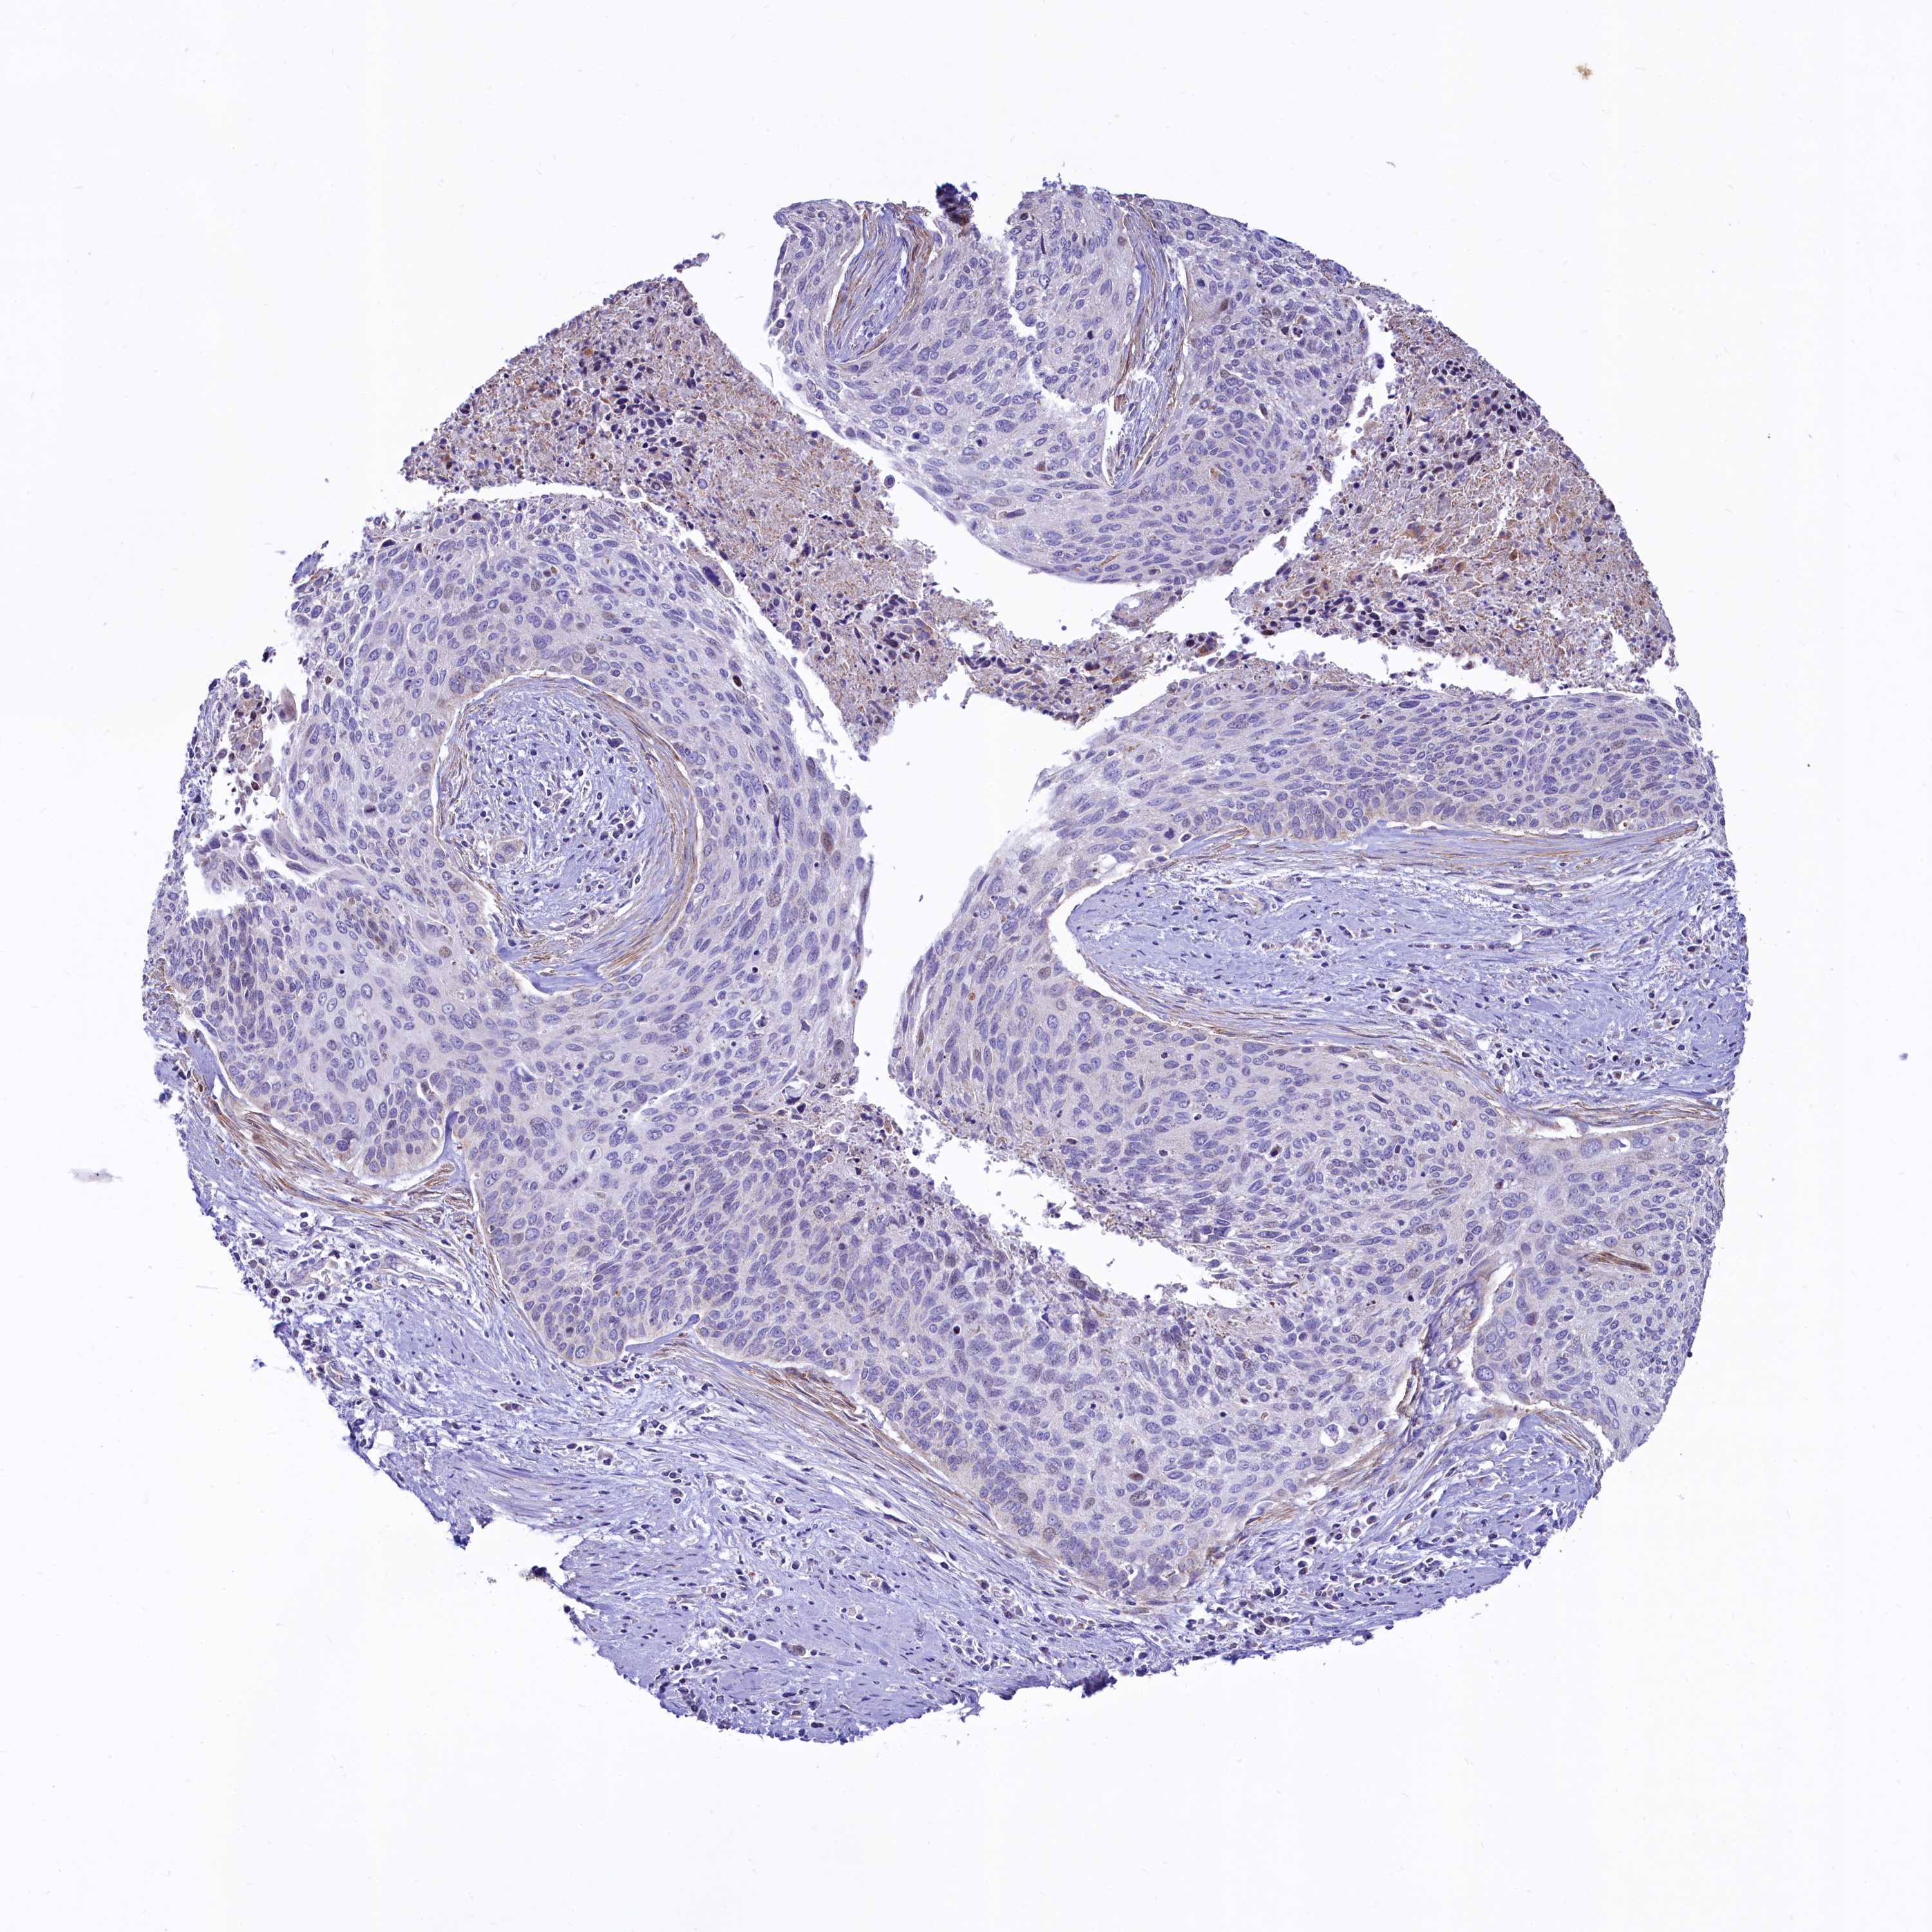

CERVICAL CANCER - Protein expressioni

A mouse-over function shows sample information and annotation data. Click on an image to view it in a full screen mode. Samples can be filtered based on level of antibody staining by selecting one or several of the following categories: high, medium, low and not detected. The assay and annotation is described here.

Note that samples used for immunohistochemistry by the Human Protein Atlas do not correspond to samples in the TCGA dataset.

Antibody stainingi

Antibody staining in the annotated cell types in the current human tissue is reported as not detected, low, medium, or high, based on conventional immunohistochemistry profiling in selected tissues. This score is based on the combination of the staining intensity and fraction of stained cells.

Each image is clickable and will lead to virtual microscopy that enables deeper exploration of all samples and also displays staining intensity scores, fraction scores and subcellular localization as well as patient and tissue information for each sample.

Antibody HPA040401

Antibody HPA043921

Staining

High

Medium

Low

Not detected

Intensity

Strong

Moderate

Weak

Negative

Quantity

>75%

75%-25%

<25%

None

Location

Nuclear

Cytoplasmic/membranous

Cytoplasmic/membranous,nuclear

Squamous cell carcinoma, NOS

Adenocarcinoma, NOS